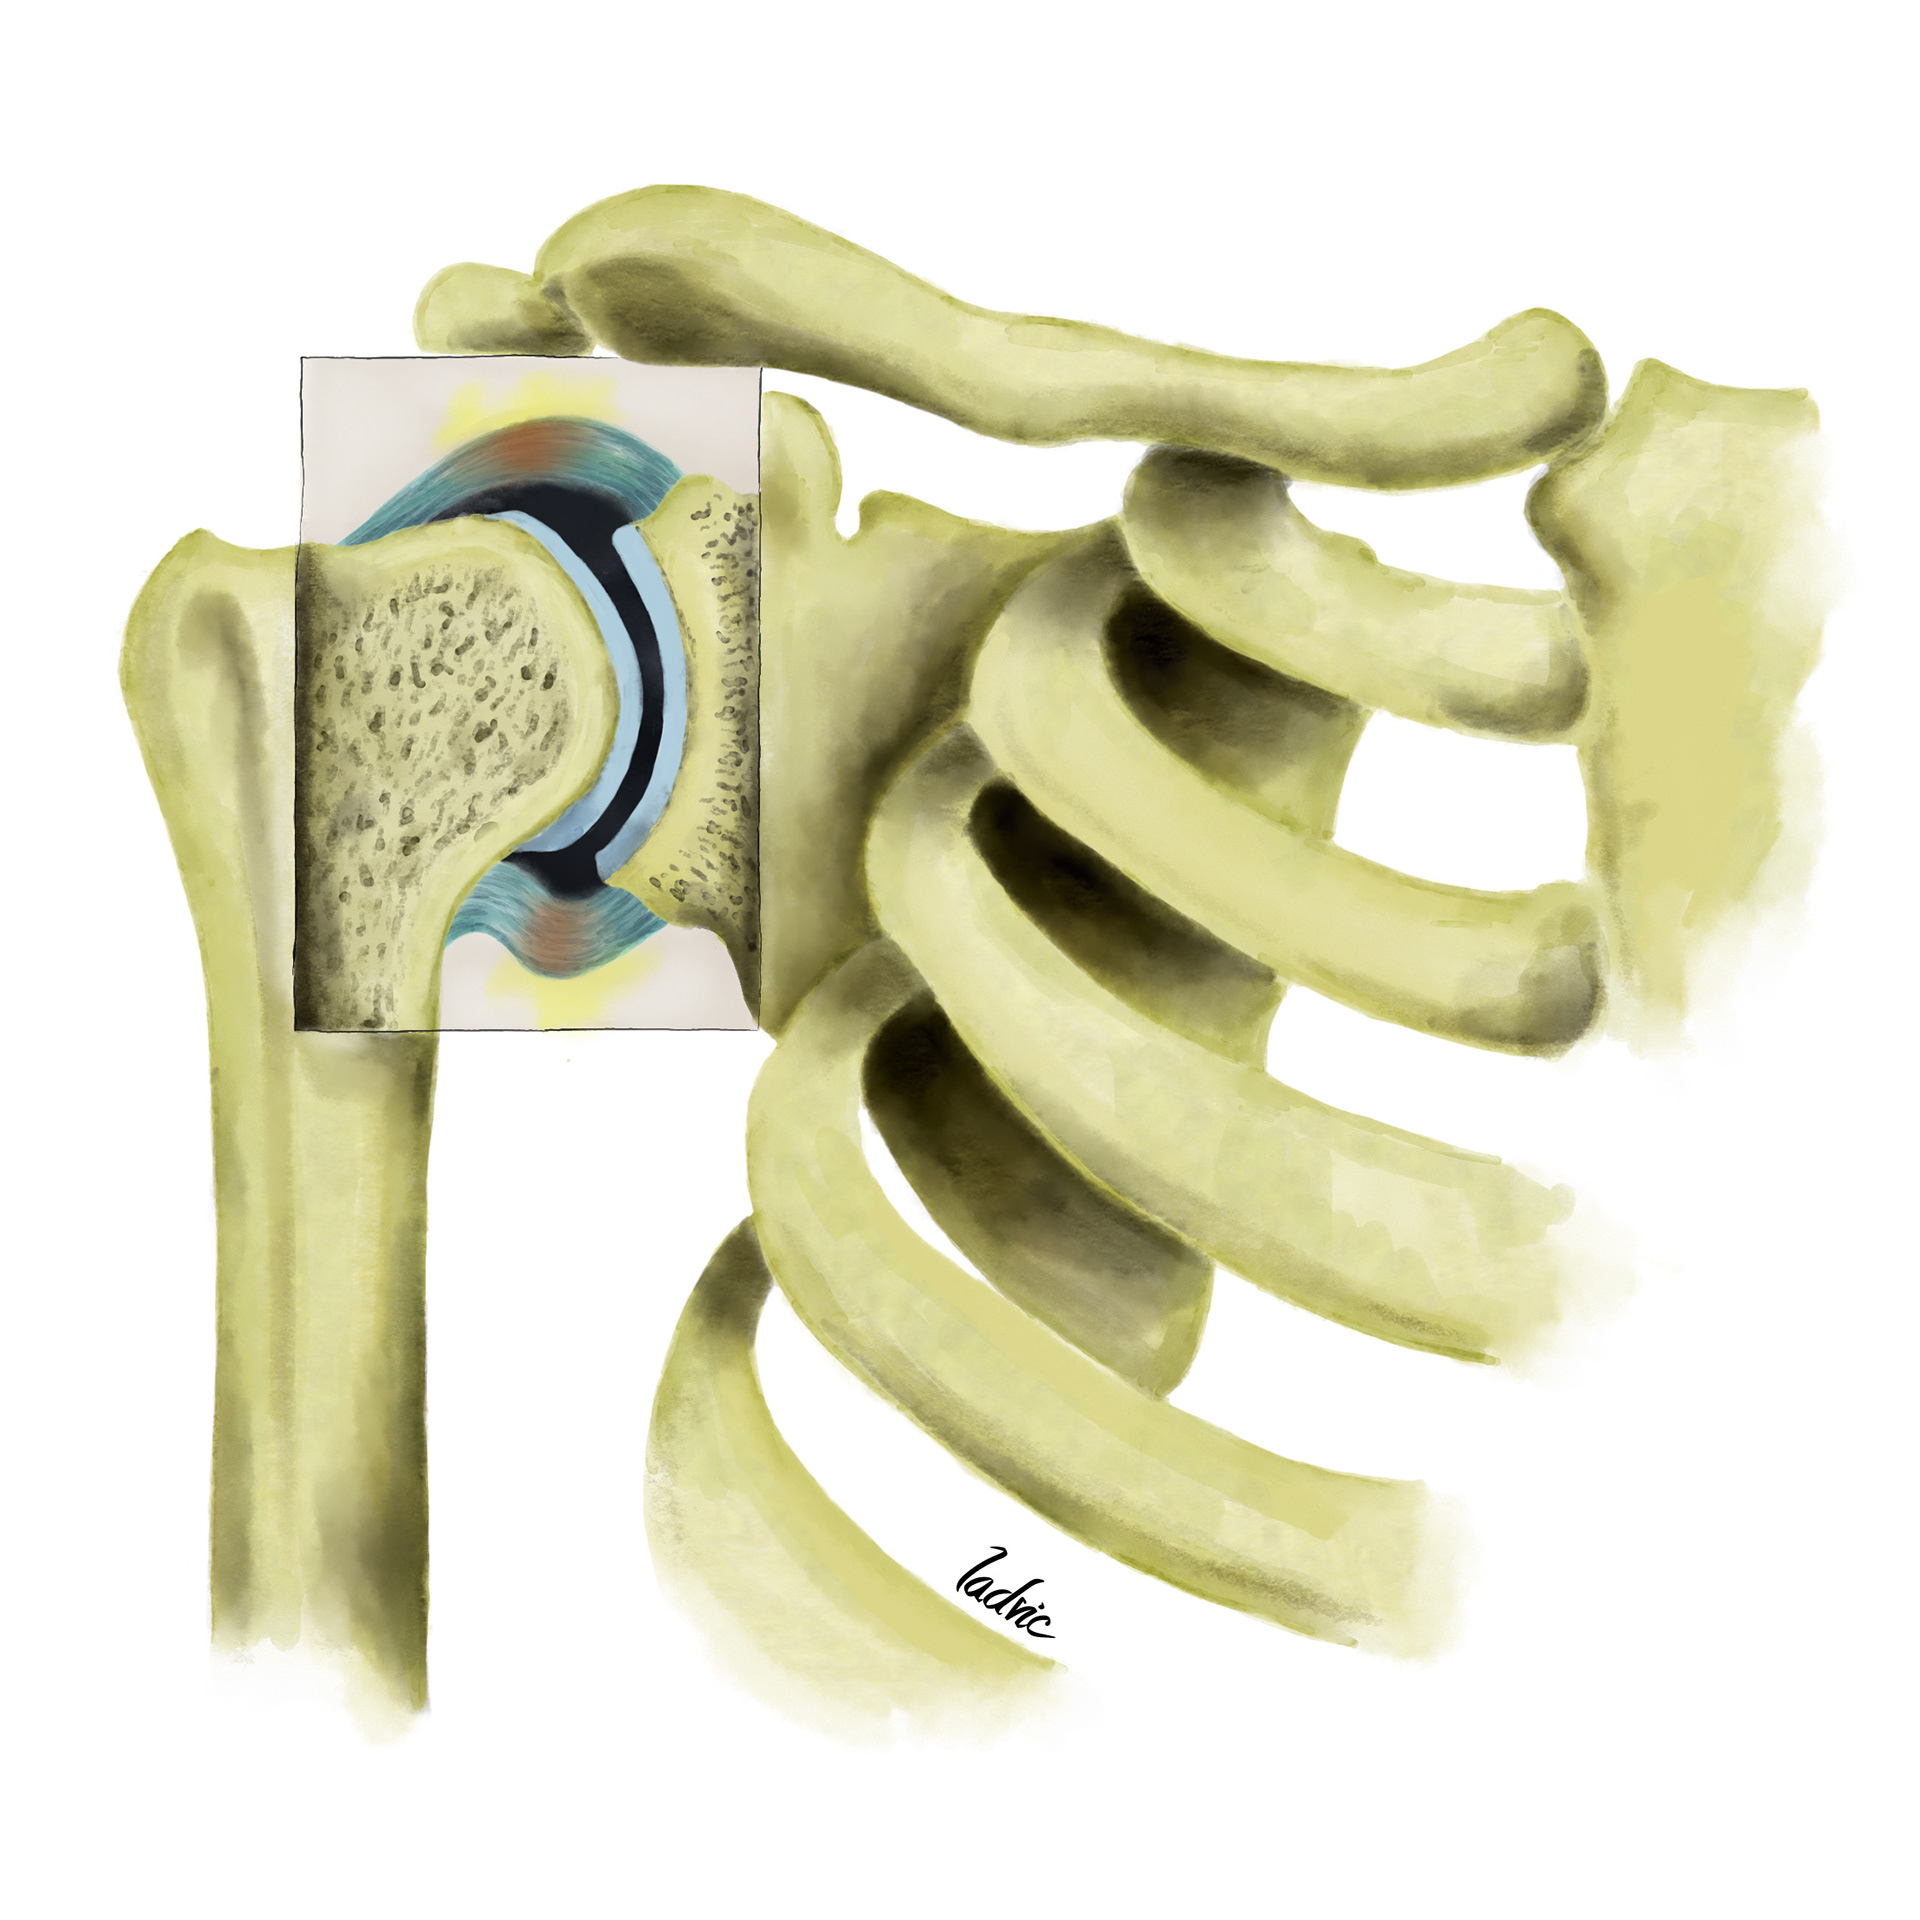

Illustration to show the vascularitation of the shoulder and diferent anatomical variants. It was made for a presentation of endovascular treatment of shoulder capsulitis.

First I draw the sketck on the iPad Pro, with the Sketchbook Software. After that, I move to Photoshop CC where, with a digital watercolour brush I painted and give the details.